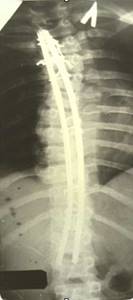

До сих пор в ортопедии принято множество методик измерения угла искривления позвоночника, и, соответственно, множество различных классификаций с разными величинами углов в градусах. Измеряется искривление так: на рентгенограмме надо провести несколько прямых линий между позвонками, а затем измерить углы между ними. В нашей стране наиболее распространена классификация, предложенная В.Д. Чаклиным. В иностранных научных источниках чаще приводится метод Дж. Кобба. Суть его заключается в следующем: на рентгеновском снимке позвоночника врач измеряет S-образное двойное искривление. В верхнем участке искривления с помощью линейки проводят две горизонтальные линии: одна над верхним позвонком, от которого идет кривизна, другая - над нижним. Если провести еще две линии, идущие перпендикулярно первым, образуется угол. Его и измеряют в градусах

Как видно, принцип измерения как у русского, так и американского профессора практически одинаковый. Разница в том, что по Чаклину, чем больше градусов, тем легче степень болезни, а по Коббу - наоборот.

Классификация выраженности сколиоза по В.Д. Чаклину (слева), по Лж. Коббу (справа) Степени тяжести сколиоза (углы искривления позвоночника, в градусах) Графический расчет на рентгенограмме: а - I степень; б - II степень; в - III степень; г - IV степень.

| По В.Д. Чаклину | По Дж. Коббу |

| I степень 180 - 175 | меньше 15 |

| II степень 175-155 | 20-40 |

| III степень 155-100 | 40-60 |

| IV степень меньше 100 | больше 60 |